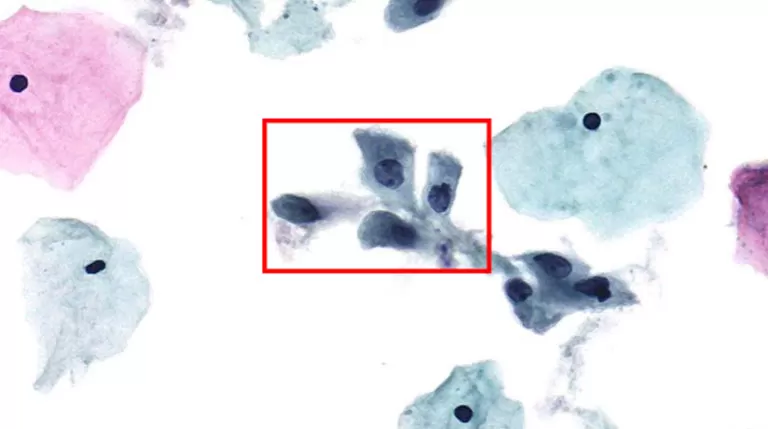

Cells may occur singly, but typically present in "crowded sheets" or "syncytial-like" aggregates with indistinct cell borders.

Mnemonic: Large hyperchromatic nuclei, high N/C ratio, pleomorphic shapes, and disordered arrangement.

Figure 1: Typical HSIL Morphology Note: Prepared via HealthSky SCTE-3600A SCT Method; Reviewed with HealthSky Patho. AI-Assisted Diagnostic System.